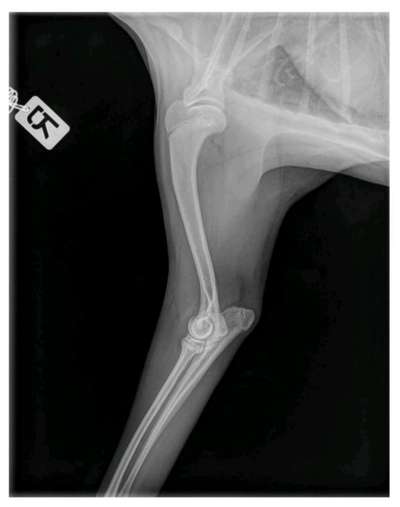

Hallo liebe Leute, Aufgrund mehrwöchiger Lahmheit vorne links bei unserem 6 Monatigen Hund (Japanspitz, eher kleine - mittelgroße Rasse) haben wir in einer Tierklinik ihn röntgen lassen und anschließend ins CT gegeben. Nun hat er laut Ärzten im Ellenbogen eine beidseitige OCD und soll zumindest auf der linken Seite operiert werden. Wir sind recht überfordert mit der Diagnose und wollen eine 2. Meinung noch einholen. Angehängt sind die Bilder. Unser Hund hatte keine Unfälle (natürlich ist er mal im Laufen auf glatten Boden daheim mal weggerutscht). Gassi sind wir immer nach der 5-10 Minutenregel pro Monat gegangen. Treppen wurde und wird er getragen. Kein wildes Spiel mit anderen Hunden. Er darf nicht allein auf die Couch. Essen bekam er Anfangs das HappyDog für Welpen, ab und zu bisschen Naturjoghurt und Buttermilch. Seit einer ganzen Weile erhält er aber nun das Welpenfutter mit Lamm von Tails and Tales. Das frisst er ohne Joghurt (das vorherige TroFu wollte er kaum noch essen, daher der Wechsel). Leckerlis bestehen, wenn, aus seinem Trockenfutter, weil er das sehr gern mag. Oder getrocknetes Lamm oder Pferd. Weil er vor einer Weile Giardien hatte bekommt er noch was zum Aufbau der gesunden Darmflora und hat inzwischen wieder guten Stuhlgang etc. Das Lahmen schwankt übrigens. Jetzt läuft er seit 2 Tagen recht gut ( Gassi ist schon seit Wochen nur an der Leine), aber das muss nichts heißen. In seiner Zuchtstätte gab es seit 20 Jahren nicht so einen Fall und ich glaube das auch. Sind hier Experten für OCD? Was habt ihr für Erfahrungen? Was sagt ihr zu unserem Befund? Macht eine OP Sinn in diesem Fall? LG Anna

Upps, das Röntgenbild ist krass!

So wie das Bild aussieht muss operiert werden und das relativ schnell.